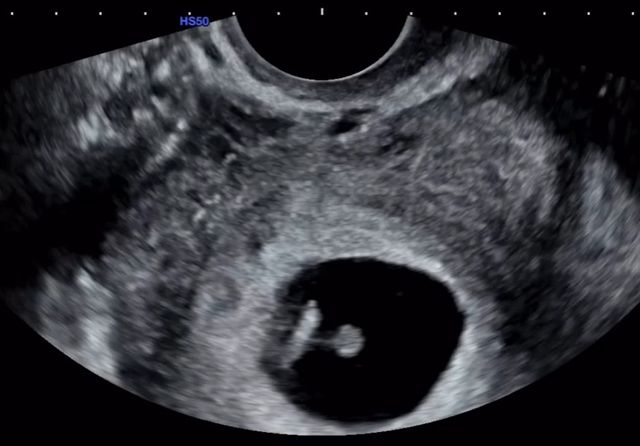

9일 오후 16기 옥순은 "16기 옥순을 시작으로 지난 2년 동안 여러분과 함께 울고 웃으며, 진심으로 소중한 시간을 보냈습니다"라고 시작되는 장문의 글과 함께 초음파 영상을 게재했다.

이어 "정말 감사하게도, 저를 있는 그대로 온전히 사랑해주는 사람을 만나게 되었고, 그 사랑이 단 한 번에 기적이 되었습니다. 네, 저… 임신했습니다!"라고 밝혔다.